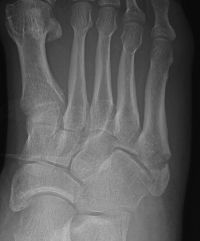

Zone 3 Fractures

Progression to nonunion of zone 3 fracture with nonoperative care

Torg Classification

| Type I | Type II | Type III |

|---|---|---|

| Acute | Delayed union | Nonunion |

|

Narrow fracture line No sclerosis No cortical reaction No periosteal hypertrophy |

Increased fracture line Both cortices Some sclerosis Some periosteal hypertrophy |

Significant sclerosis Significant cortical hypertrophy |